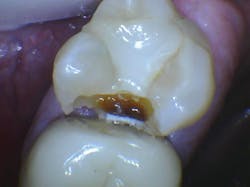

Open contact areas

Contact areas should be broad and flat to prevent food impaction. Leaving a contact area open is almost a sure invitation for caries to form (figure 3). Suggest to your lab that you want broad, flat, tight contact areas on your crowns. It is far easier to reduce a contact area than to add to a deficient one. The lab technician can meet most of these characteristics easily by adjusting the computer setting for the contact area.

If the patient has tooth mobility, tell the lab technician to make the contacts very tight, and then adjust them in the mouth if necessary.